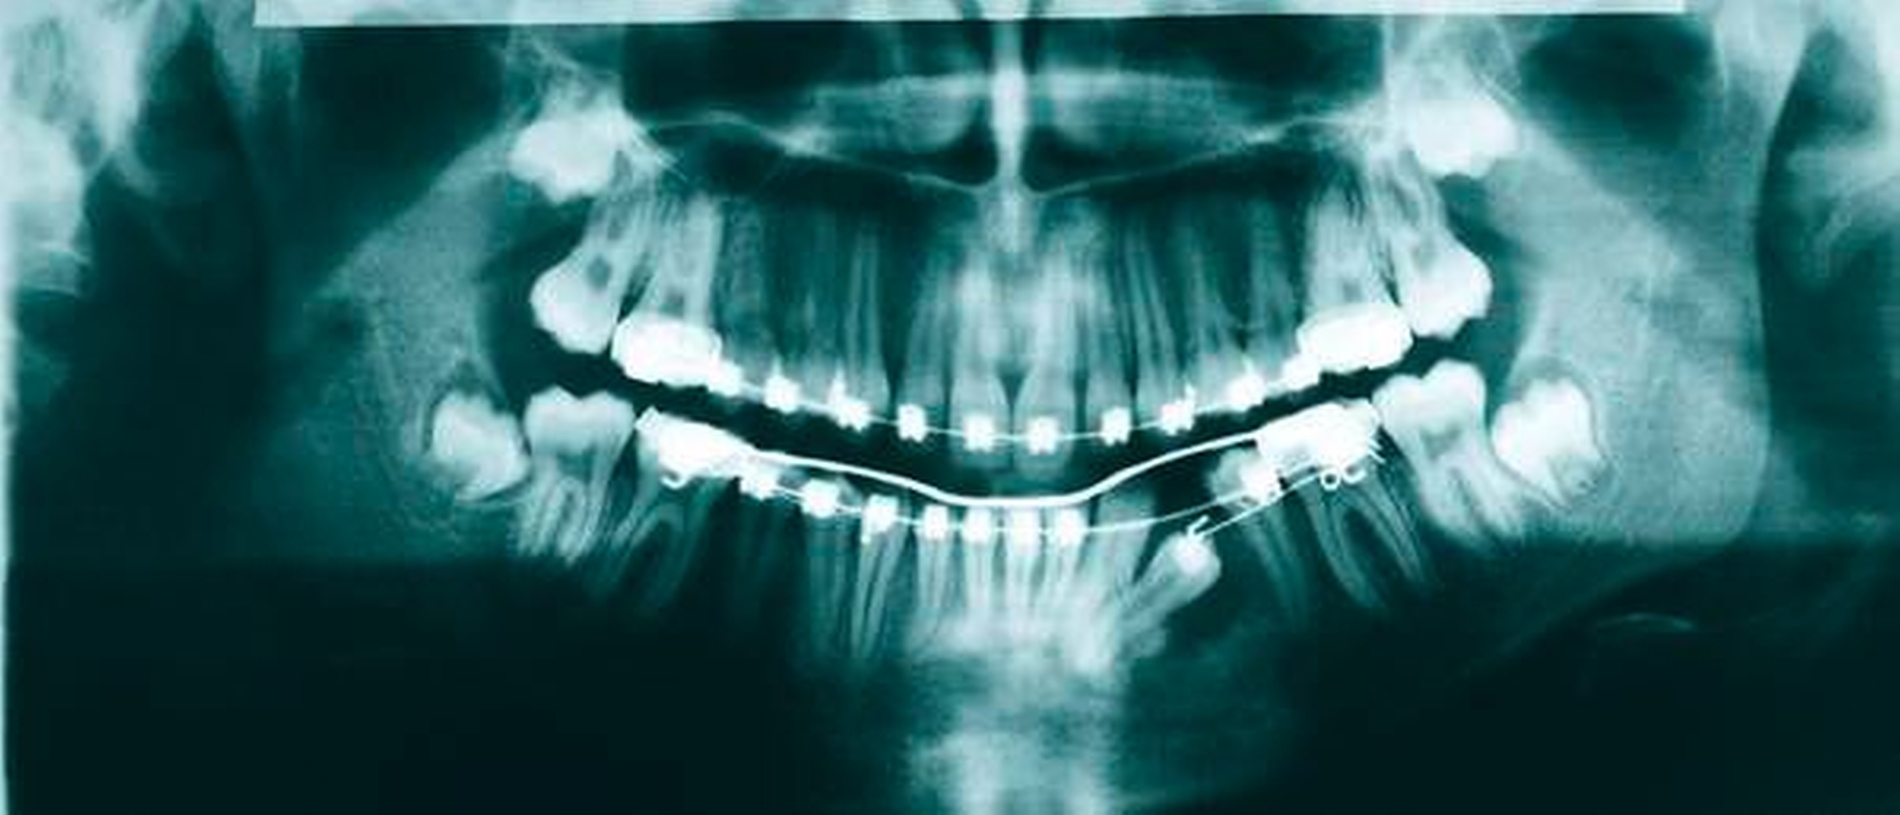

Im Orthopantomogramm imponierte eine Aufhellung, die sich regio 33 bis 35 nahezu über die gesamte vertikale Dimension des Unterkiefers erstreckte und die Krone des Zahnes 34 einschloss. Dieser lag horizontal verlagert, die Krone nach distal orientiert über die Wurzeln der Zähne 41 bis 74 projiziert. Zudem konnten die Anlagen der vier Weisheitszähne mit drohendem Engstand sowie ein nach mesial angulierter Zahn 24 befundet werden (Abbildung 4).

Die zwischenzeitliche Entfernung der Weisheitszähne diente der Okklusionsstabilisierung und der Prophylaxe eines Engstands (Abbildungen 6 bis 11). Technisch wurden ein Lingualbogen, ein Powerarm zur Elongation und im Verlauf der Behandlung eine feste Apparatur verwendet. An 34 wurde ein Bracket angebracht, ein Supercabble-Bogen als Huckepack-Bogen sowie ein SS-16x22-Trägerbogen eingesetzt.

Im abschließenden OPG war der Zahn 34 regelgerecht eingeordnet, die nach distal deviante Wurzelspitze ist aller Wahrscheinlichkeit nach der Verlagerung geschuldet (Abbildung 8).